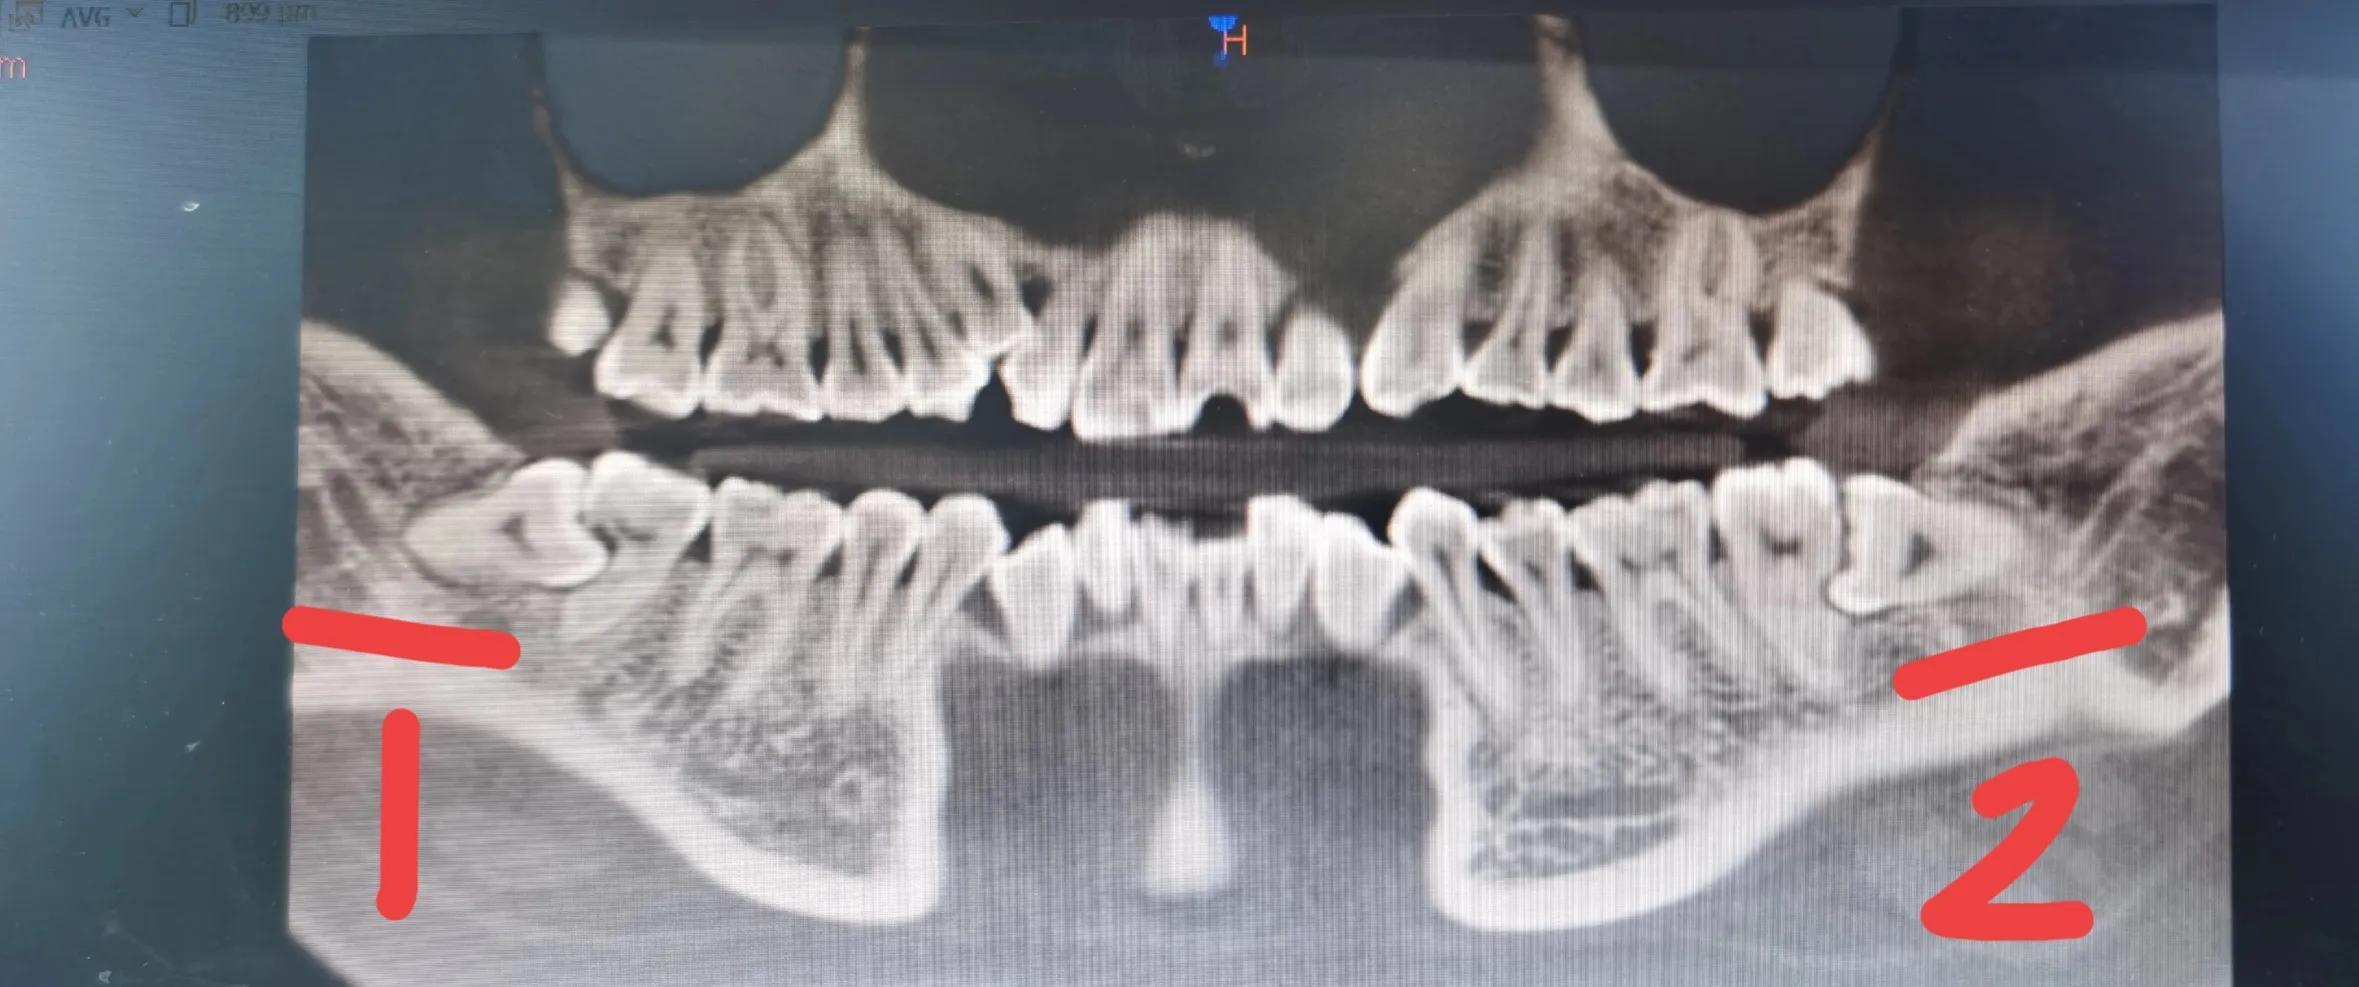

所以我对拔牙心有余悸。但是我的牙齿状况容不得我再有犹豫,必须得去拔另外一颗,要把嘴里三颗的智齿都拔掉。我的两颗大牙都被旁边的智齿顶坏了,问了很多个医院和诊所的医生,都说被顶坏的大牙没办法保住,只能暂时用着,如果发炎了或者疼痛严重起来,只有把大牙拔掉,重新种植牙齿。所以必须当机立断去把另外一颗严重的智齿。

目前这两颗都已拔掉

最后还重新拍了片进行复查,看有没有多余的碎牙齿没有拔出,结果拔的很干净。后来我去药店买了消炎药和奥硝唑片,也备了一些止疼药,但是止疼药从来没用过。